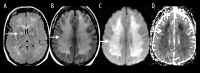

Toxic leukoencephalopathy results from damage to the white matter caused by various toxins. It manifests itself as white matter signal abnormalities with or without the presence of restricted diffusion. These changes are often reversible if the insulting agent is removed early, with the exception of posthypoxic leukoencephalopathy that can manifest itself 1-2 weeks after the initial insult. However, many other potential causes of white matter signal abnormalities can mimic the changes of toxic leukoencephalopathy. Thus, familiarity with the causes, clinical presentation and particularly imaging findings of toxic leukoencephalopathy is critical for early treatment and improved prognosis. The purpose of this pictorial essay is to familiarize the reader with the various causes of toxic leukoencephalopathy along with its differential diagnoses and mimics.